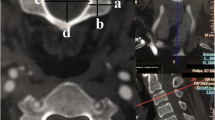

Determination of the plane of the intervertebral foramen (Fig. 1)

In order to determine the plane of the intervertebral foramen, the 3DMRP center was put in the center of the pedicle of the superior vertebrae, with an axial plan parallel to the underlying vertebrae superior endplate. Rotation was controlled so that the sagittal axis was parallel to the pedicle axis (Fig. 1a). After locating the center of the overlying pedicle, sagittal, coronal and axial axis were kept the same, but were placed in the center of the intervertebral foramen (Fig. 1b).